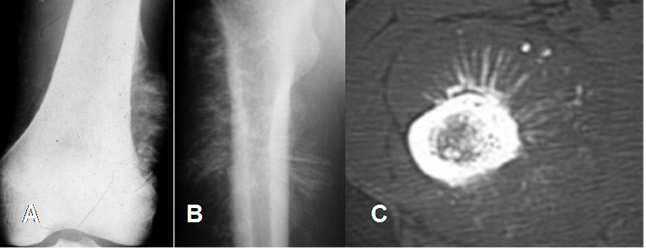

Fig 41. Reacción perióstica agresiva del osteosarcoma.

A: Rx AP. Reacción perióstica en peine.

B: Rx AP y C: TAC axial. Reacción perióstica en sol naciente.